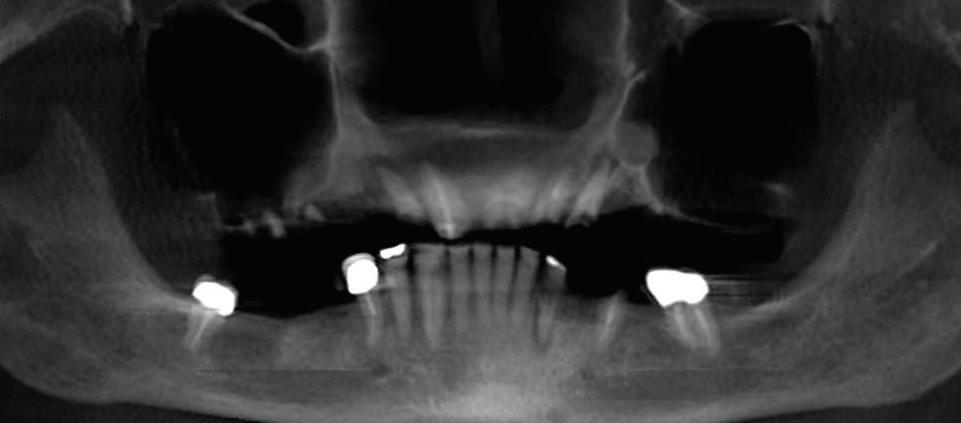

Restoring Smiles With Surgical Dental Implant Placement

Missing teeth can affect not only your smile but also your ability to speak and chew properly. Dental implants are a long-term solution that closely mimics natural teeth, offering both aesthetic and functional benefits. Understanding the surgical implant placement process can help individuals considering this option make an informed decision.

What Is Surgical Implant Placement?

Dental implant placement is a minor surgical procedure designed to replace missing teeth with artificial roots made of titanium. The implant is inserted into the jawbone, where it naturally integrates through a process called osseointegration. This provides a sturdy foundation for a

The procedure is typically performed in multiple stages. First, the periodontist surgically places the implant into the jawbone. Over the next few months, the bone fuses with the implant, ensuring a secure fit. Once the healing process is complete, an abutment is attached, followed by a custom-made crown that blends seamlessly with the surrounding teeth.

Who Is a Candidate For Dental Implants?

Most healthy adults with missing teeth can be candidates for dental implants, but certain factors influence eligibility. Ideal candidates should have:

• Sufficient jawbone density to support the implant, and vertical and horizontal dimensions to accommodate the proper sized implant that best represents the missing tooth.

• Sufficient spacing to allow for crown, bridge, or denture fabrication on top of the proposed implant.

• Healthy gums free of active periodontal disease

• Good overall health, as conditions like uncontrolled diabetes and smoking/vaping may affect healing

• A commitment

to

maintaining oral hygiene

For those with inadequate bone volume, bone grafting procedures can often prepare the jaw for implant placement.

The healing process generally takes a few months, allowing the implant to fully integrate with the bone before the final restoration is placed. Once complete, the implant functions like a natural tooth, providing stability and durability for years to come.

A Long-Term Investment In Oral Health

Dental implants not only restore a confident smile but also help maintain facial structure and prevent bone loss associated with missing teeth. For those seeking a permanent and natural-looking tooth replacement, consulting with a qualified periodontist can help determine the best path forward.